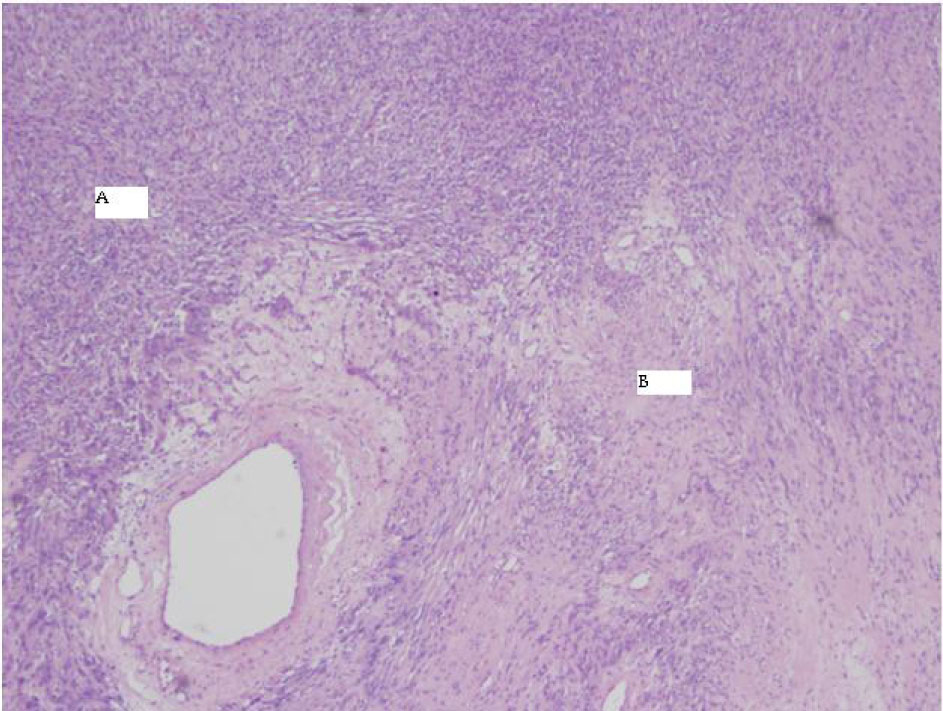

The final pathology demonstrated a 23 × 14.5 × 13.5 cm, 2590 grams, multiloculated, cystic mass (Fig. 4, 5) consistent with ancient schwannoma characterized by a proliferation of spindle cells (Fig. 6), Antoni type A and type B (Fig. 7) and strong positivity for S-100 protein (Fig. 8). The post-operative period was uneventful and patient was discharged home day 5 after surgery. At 11-month follow-up, the patient is free from recurrence.

![]() Click for large image | Figure 6. 4X HE Antoni A and B. |

Microscopically, the tumor contains varying proportions of Antoni A and B histologies [10]. Antoni-A is composed of spindle cells with elongated nuclei, forming interlacing bundles with focal nuclear palisading and lacks mitotic figures [11]. However, Antoni-B is less cellular and lacks distinct architectural features [10, 11]. Strong positively for S-100 is a requisite for diagnosis [11]. Since fine needle aspiration or biopsy cannot provide a definitive histological diagnosis [8], surgical resection is typically recommended to confirm diagnosis, obtain local control and mitigate symptoms when present.